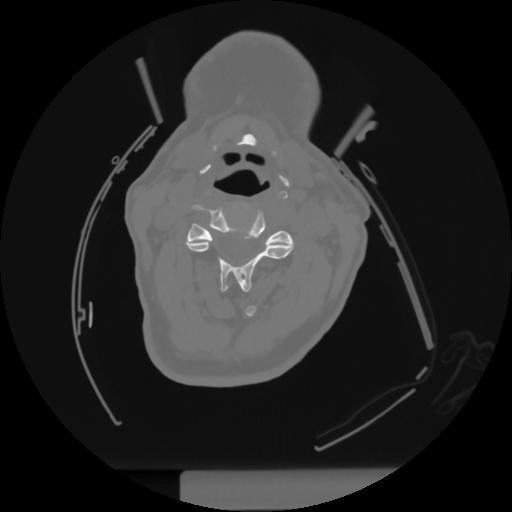

12 P.BLANDAS,,Vol,0.5,P.BLANDAS,,